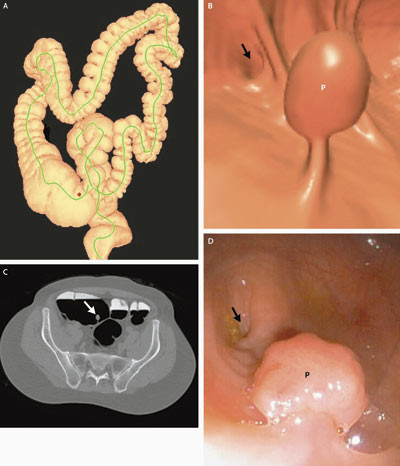

Den største og så langt mest positive publikasjonen inkluderte 1 233 personer med middels risiko for kolorektal kreftsykdom og som fikk utført CT-kolografi som screening (9) (fig 1). Det ble benyttet et tømmingsregime med fosforalløsning, manuell innblåsning av romluft, fekal merking, multidetektor-CT og gransking primært med tredimensjonal virtuell koloskopi utført av erfarne radiologer. Sensitivitet per pasient for adenomatøse polypper ≥ 8 mm var 94 %. 55 polypper ≥ 5 mm ble påvist av kun CT-kolografi primært og verifisert først ved annen gangs koloskopi. De fleste av disse var lokalisert bak en tarmfold eller nær anus. Totalt sett var det ingen signifikant forskjell i sensitivitet mellom CT-kolografi og koloskopi for adenomatøse polypper ≥ 8 mm. To av polyppene var maligne. CT-kolografi påviste begge, mens en 11 mm stor malign polypp ble oversett ved første gangs koloskopi. For såkalte flate adenomer isolert sett var sensitiviteten ved CT-kolografi 80 %. Pasienttiden ved CT-kolografi var i gjennomsnitt 14,1 minutter og ved koloskopi 31,5 minutter.

CT-kolografi synes å være spesielt godt egnet etter inkomplett koloskopi, helst utført samme dag. Pasienten vil i så fall allerede være forhåndstømt og ha en del gass i tykktarmen. Merbelastningen ved en CT-kolografi vil i så måte være beskjeden. I et materiale på 40 ufullstendige koloskopier ble det rapportert at CT-kolografi gav en fullstendig fremstilling av tykktarmen i over 90 % av tilfellene (31). Egne erfaringer som er gjort på denne type problemstilling, er også positive (fig 2). Når koloskopi er ufullstendig på grunn av strikturerende cancer, vil det kunne være hensiktsmessig at den supplerende CT-kolografiundersøkelsen utføres med tilpasset stråledose og intravenøs kontrast for eventuelt å påvise metastaser til lever og abdominale lymfeknuter.